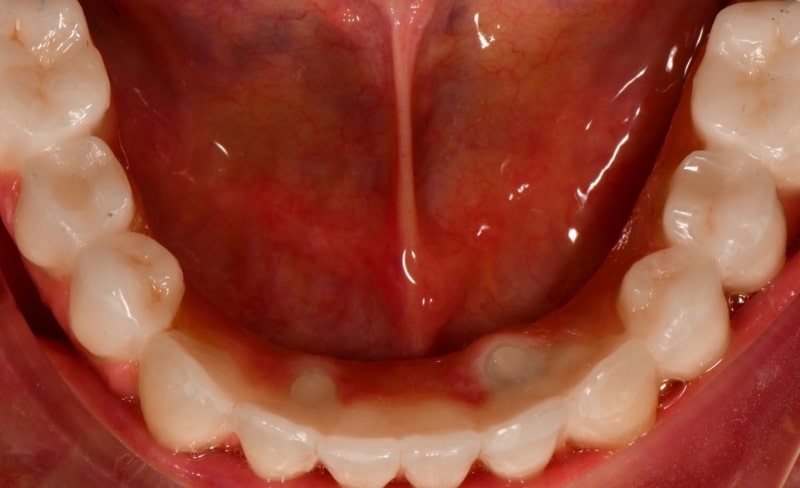

Upper and lower all-on-4 dental implants to restore function and aesthetics.